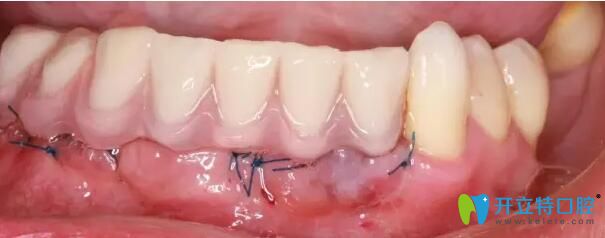

南通摩爾口腔牙齒種植后

(圖二) 采用3D數(shù)字導板技術(shù)植入種植體后 即刻完成臨時固定牙修復